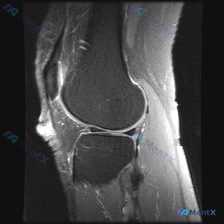

刚整理了一个很有代表性的影像读片病例,和大家分享一下思路,这个病例其实很能反映日常读片容易踩的坑。 病例基础信息 本次读片对象是单张膝关节矢状位T1加权MRI影像,临床提示需要排查是否存在可视化软骨异常。 影像基础评估(基于当前T1图像) 先给大家整理下客观观察结果: 1. 骨性结构:股骨远端、胫骨...

看到这个有意思的病例,整理一下完整分析思路分享给大家。 病例影像基本信息 这是一张膝关节矢状位T1加权MRI图像,扫描范围覆盖髌股关节及部分胫股关节,图像对比度良好,可以清晰分辨解剖结构。 我们先按系统读片流程一步步来: 1. 骨骼与对线:股骨远端、胫骨近端、髌骨骨皮质连续,没有明显骨折线;骨髓信号...

刚整理了一份有意思的膝关节MRI读片病例,核心问题是单张T1矢状位图像提示「软骨异常」,这里把整个分析思路整理出来和大家交流。 一、病例基本影像信息 这是一张膝关节正中偏内侧矢状位的T1加权MRI图像,图像质量良好,无明显伪影,可清晰观察髌骨、股骨远端、胫骨近端、后交叉韧带及半月板结构。 二、系统性...

今天分享这张膝关节矢状位T2加权MRI的分析,刚好能练一练单关节积液合并软骨信号异常的诊断思路,整理出来和大家讨论。 一、影像基本信息 这是单张膝关节矢状位T2加权MRI,先给大家梳理明确的影像发现: 1. 整体影像质量合格,各解剖结构清晰,T2序列信号对比正常 2. 骨结构:股骨远端、胫骨近端骨皮...